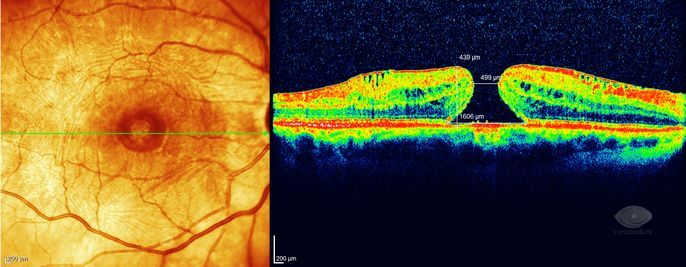

Диагностика зрения: Когерентная томография сетчатки

Раздел: Фотоальбом решений